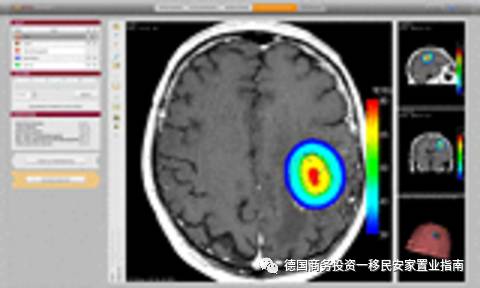

Magforce 研发了基于纳米技术的实体瘤疗法(NanoTherm)。此疗法将超顺磁性纳米颗粒直接引入到肿瘤,然后通过交变磁场振动并加热超顺磁性纳米颗粒,从内部治疗肿瘤。

此疗法所使用的交变磁场机(Magnetwechselfeldapplikator)已经在欧洲获得了CE认证,现在将在欧洲市场推广。Magforce公司正致力于将此疗法加入保险公司报销范围内。虽然该疗法在欧洲已获得批准,但作为主要市场之一的美国,对此项疗法的审核仍在进行中。